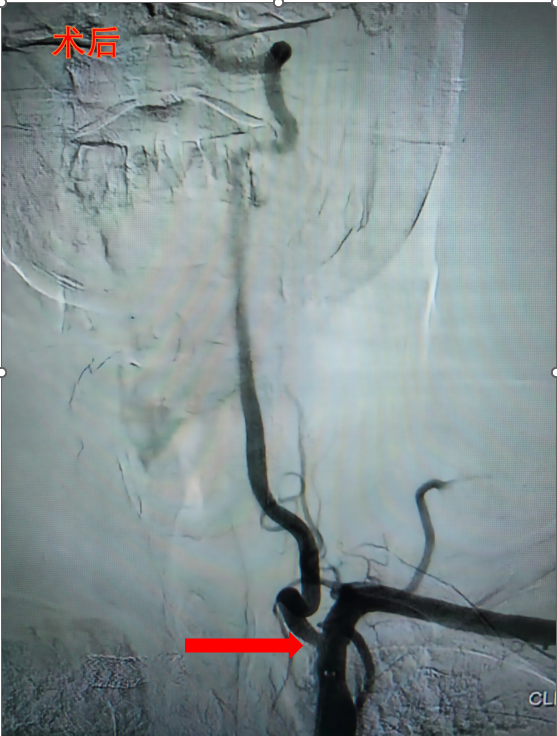

近日,兰州石化总医院(甘肃中医药大学第四附属医院)神经内科团队成功应用单纯药物涂层球囊扩张术,为一位椎动脉开口狭窄患者实施介入治疗。该项技术的成熟开展,标志着医院在脑血管介入领域已具备“介入无植入”先进技术的全面临床应用能力,为区域内椎动脉狭窄患者提供了更优治疗选择。

此次手术的成功实施,得益于医院神经内科团队在脑血管介入领域的深厚积累。术前,团队通过高分辨率磁共振管壁成像等先进检查手段,精确评估病变性质;术中凭借丰富的经验,精准控制球囊扩张的压力与时间;术后建立了系统的随访管理体系,确保患者获得全程化医疗照护。

接受该手术的患者术后恢复顺利,困扰多时的头晕症状明显缓解,术后三天即康复出院。经一个月随访复查,患者椎动脉血流通畅,无再狭窄迹象,日常生活质量得到显著提升。